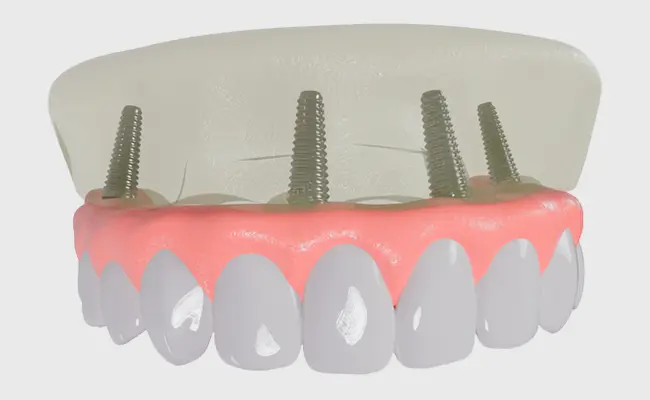

If you are seeking a solution for fixed restoration of your teeth, this is the implant procedure known as All-on-4. During this procedure, four specialized dental implants are placed to keep the appliance in place and supported. These four implants can anchor a complete arch, either your upper or lower full of teeth. If you’re currently wearing dentures and don’t think it performs well, then consider the All-on-4 option – a solution that has been in place for years with a high success rate.

But with the new All-on-4 procedure, it’s all done — extraction, placement of implants and artificial teeth — now in only one day. Whereas way back when, to replace a denture with a full arch, you would have needed six to ten implants just to support all the teeth and create adequate strength stability. Now it turns out that simply using the laws of physics along with stronger materials, when you place your implants at an angle they increase their strength so therefore can be used fewer number of them.

Two anterior implants upright and two posterior at a 45-degree angle. Because of the special position of these implants, All-on-4 does not involve any bone grafting due to atrophy. By employing only four implants, the procedure also minimizes discomfort. A prototype bridge is placed over the implants, which can be used as normal teeth until your permanent bridge has been fabricated in the dental lab and eventually cemented permanently.

The All-on-4 immediate implant consists of several components. The implant posts are made from titanium, as it is scientifically proven to be capable of grafting with the human bone.

The fixtures used for implant are constructed to serve as the roots of your own teeth and titanium material allows bone to fuse and attach itself with the post.

An abutment or extension will be added to each of these structures to reach the surface of the gum and finally a restorative bridge is placed on all four extensions.